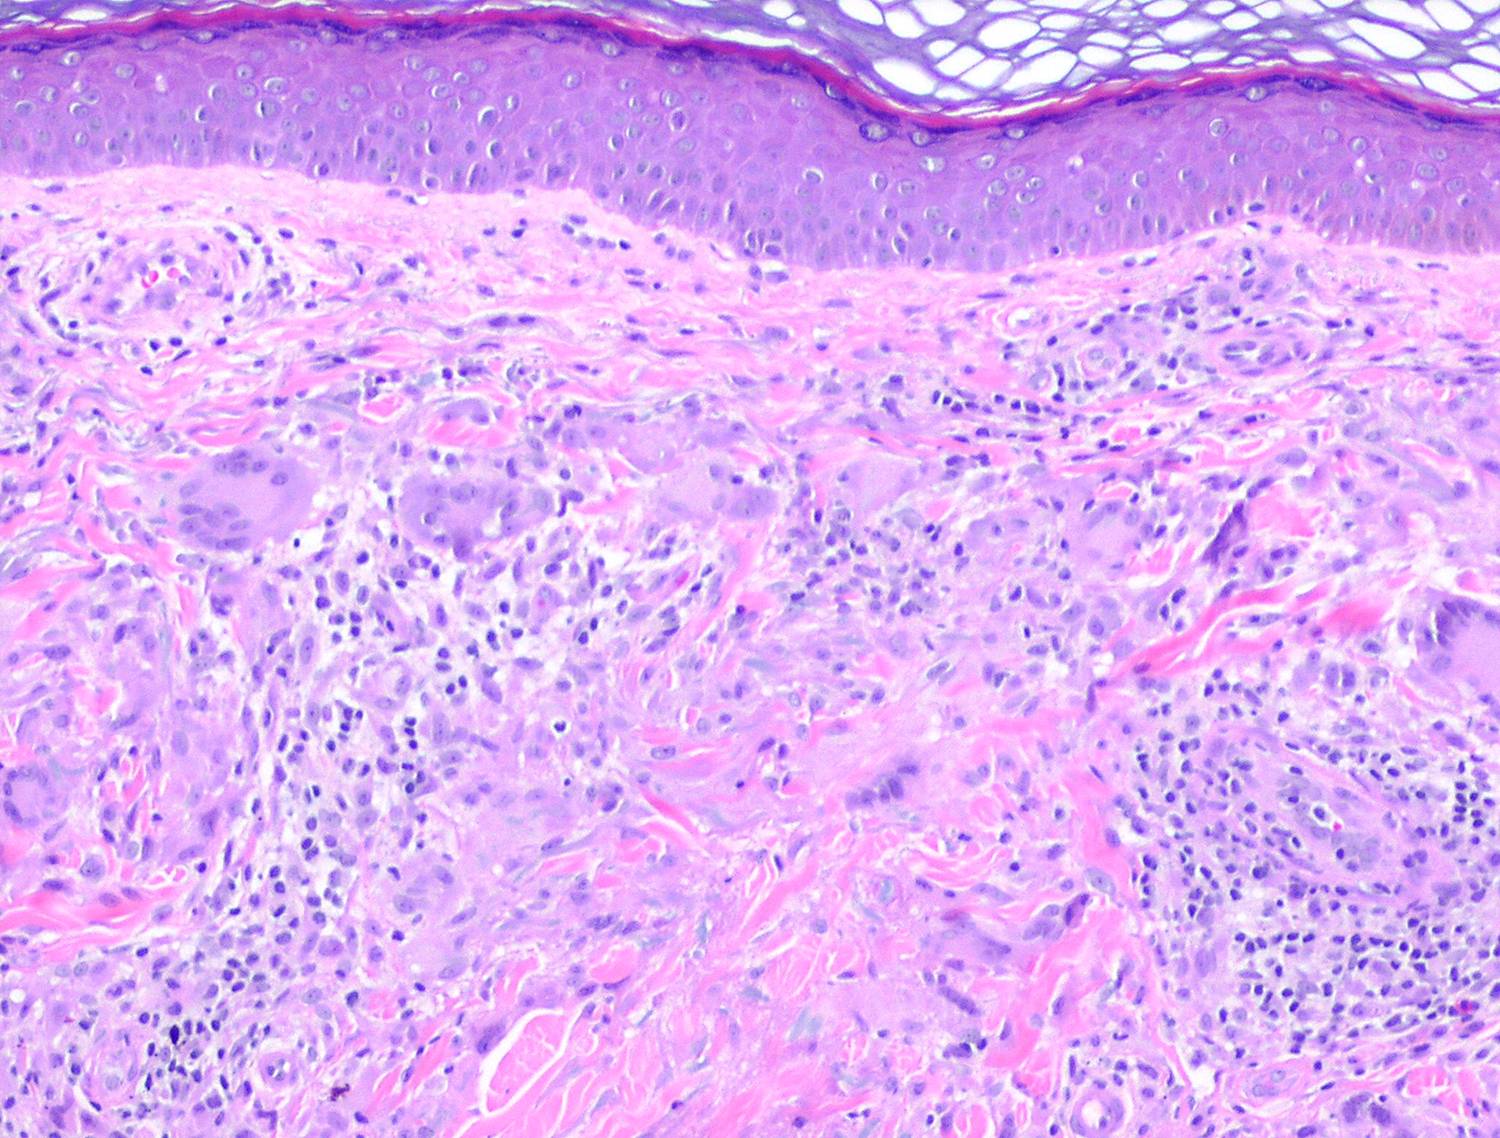

Annular elastic granuloma =الورم الحبيبي الحلقي المرن